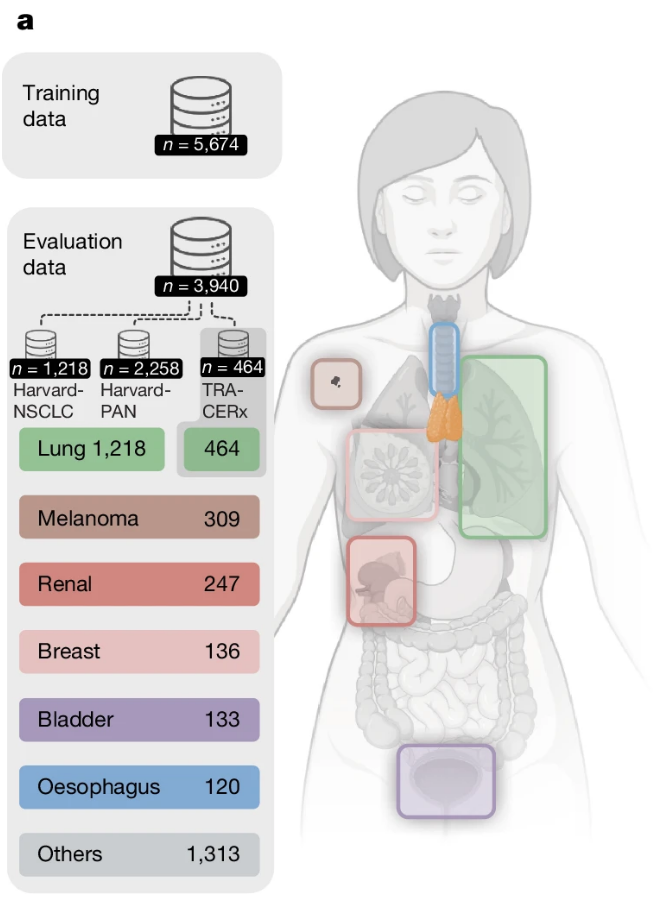

| ▲ a. 훈련 데이터 및 실제 임상 데이터를 기반으로 한 Harvard-NSCLC 및 Harvard-PAN(흑색종, 신장암, 유방암, 방광암, 식도암, 기타) 평가 코호트(총 n=3,476)에 대한 개요. Harvard-PAN 코호트 중 각 종양 유형별 환자 수가 100명 미만인 경우는 '기타'로 통합했다. 모든 환자는 Dana-Farber Harvard Cancer Center(DFHCC)에 면역항암요법을 받았다. 외부 및 생물학적 검증은 전향적으로 수집된 TRACERx NSCLC 코호트(n=464)에서 수행되었다. (출처:Published: 18 March 2026 / Thymic health and immunotherapy outcomes in patients with cancer) |